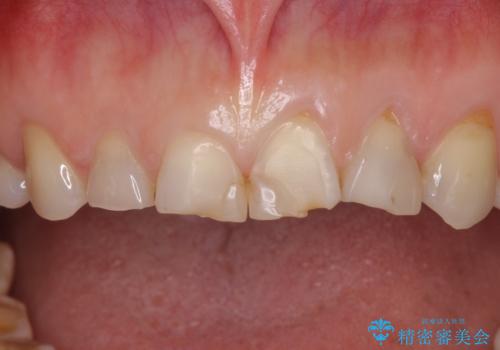

欠けてガタガタの前歯 オールセラミッククラウンによる補綴治療

- 咬み合わせと度重なる応急処置の繰り返しにより、前歯がガタガタになってしまったとのことで来院された患者様です。

4本の前歯が気になっていたので、全てをオールセラミッククラウンにて補綴治療を行うこととしました。